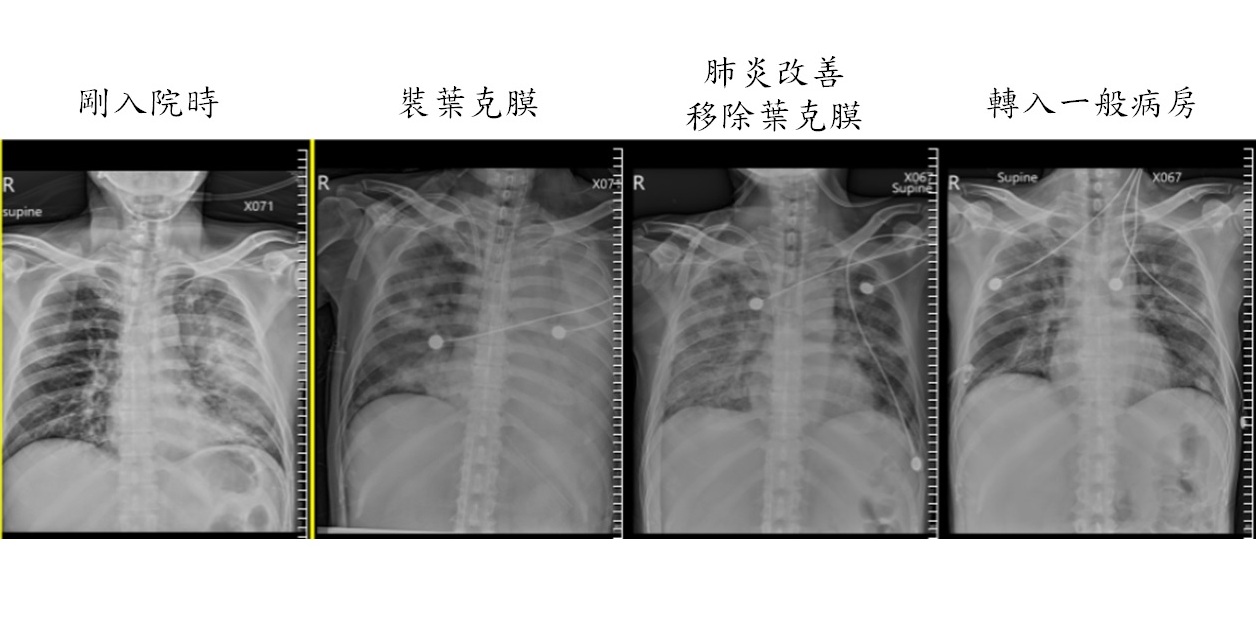

47歲的徐先生從25歲就開始抽菸,一日因出現發燒、呼吸困難、尿量減少、咳血痰、寒顫等症狀而到大千綜合醫院急診就醫,醫師檢查發現其血氧過低,且胸部X光顯示肺部雙側有大片肺炎,因此安排進入加護病房治療。當天肺炎情況突然惡化,藥物及呼吸器無法改善其病況,因此醫護團隊立即使用葉克膜治療,在將近一個月的時間,終於成功改善肺炎狀況並移除葉克膜,兩週後轉出一般病房,並於一週後順利出院。

個案徐先生到院時,X光檢查雙側肺部都呈現白色,即為典型的肺炎現象,加上當天肺炎狀況突然轉趨嚴重,導致肺部無法正常運作,因此醫療團隊在第一時間使用葉克膜治療,藉由人工心臟將病人的血液從靜脈引出,再透過人工肺臟將缺氧血中的二氧化碳移除,並加入血中氧氣後,回到病人的動脈或靜脈內。在醫護團隊24小時不間斷的照顧下,順利在第28天改善肺炎情況並成功移除葉克膜。出院當天,徐先生及家屬非常感謝醫護團隊的照護,鄭恩宗主任也代表院方送上營養品,讓徐先生帶著祝福健康返家。